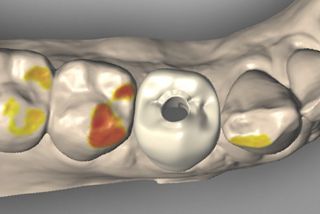

Abb. 1 - Klinische Ausgangssituation mit dem frakturierten Zahn 44 von okklusal.